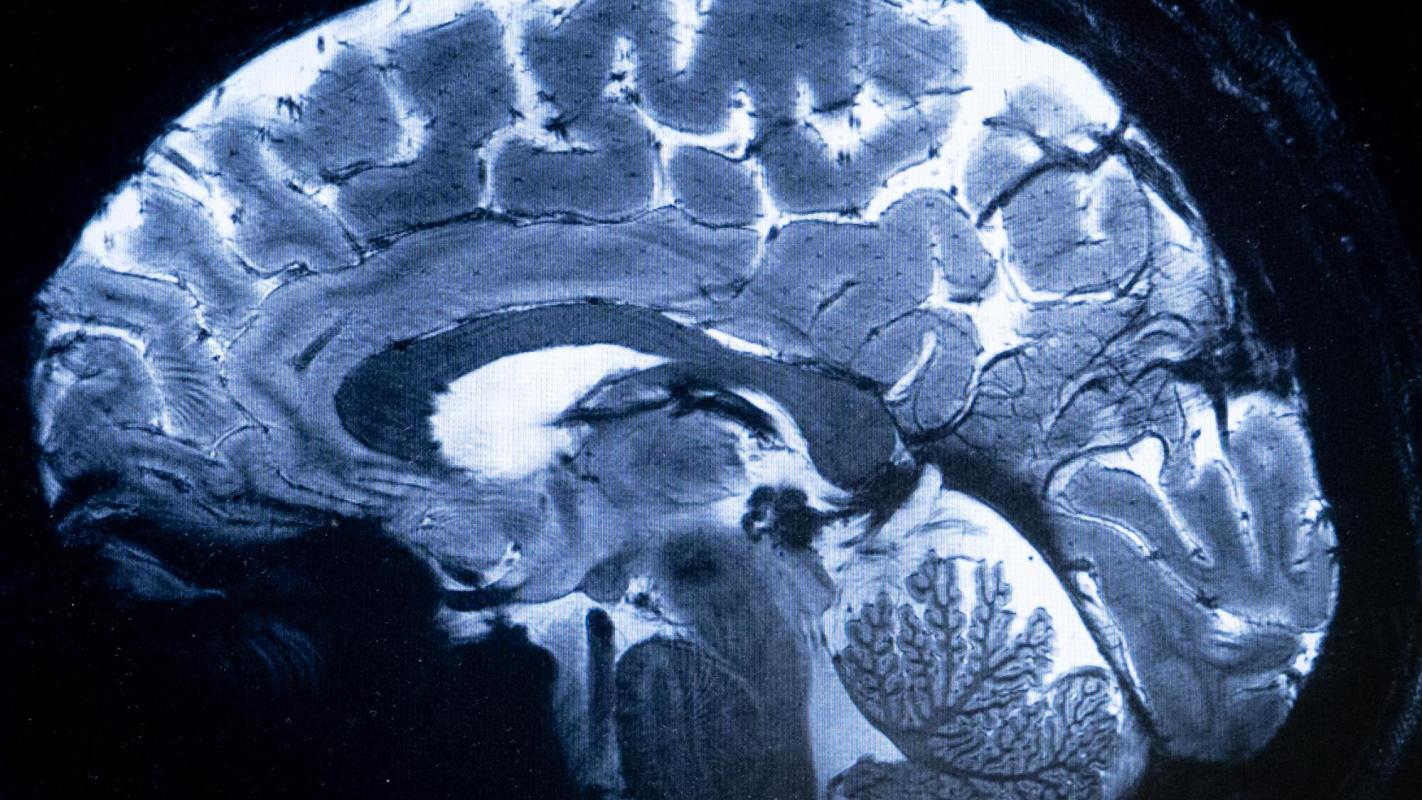

"Podríamos estar haciendo diagnósticos prematuros": Nuevos hallazgos sobre qué pasa en el cerebro al morir

AFP - Cerebro